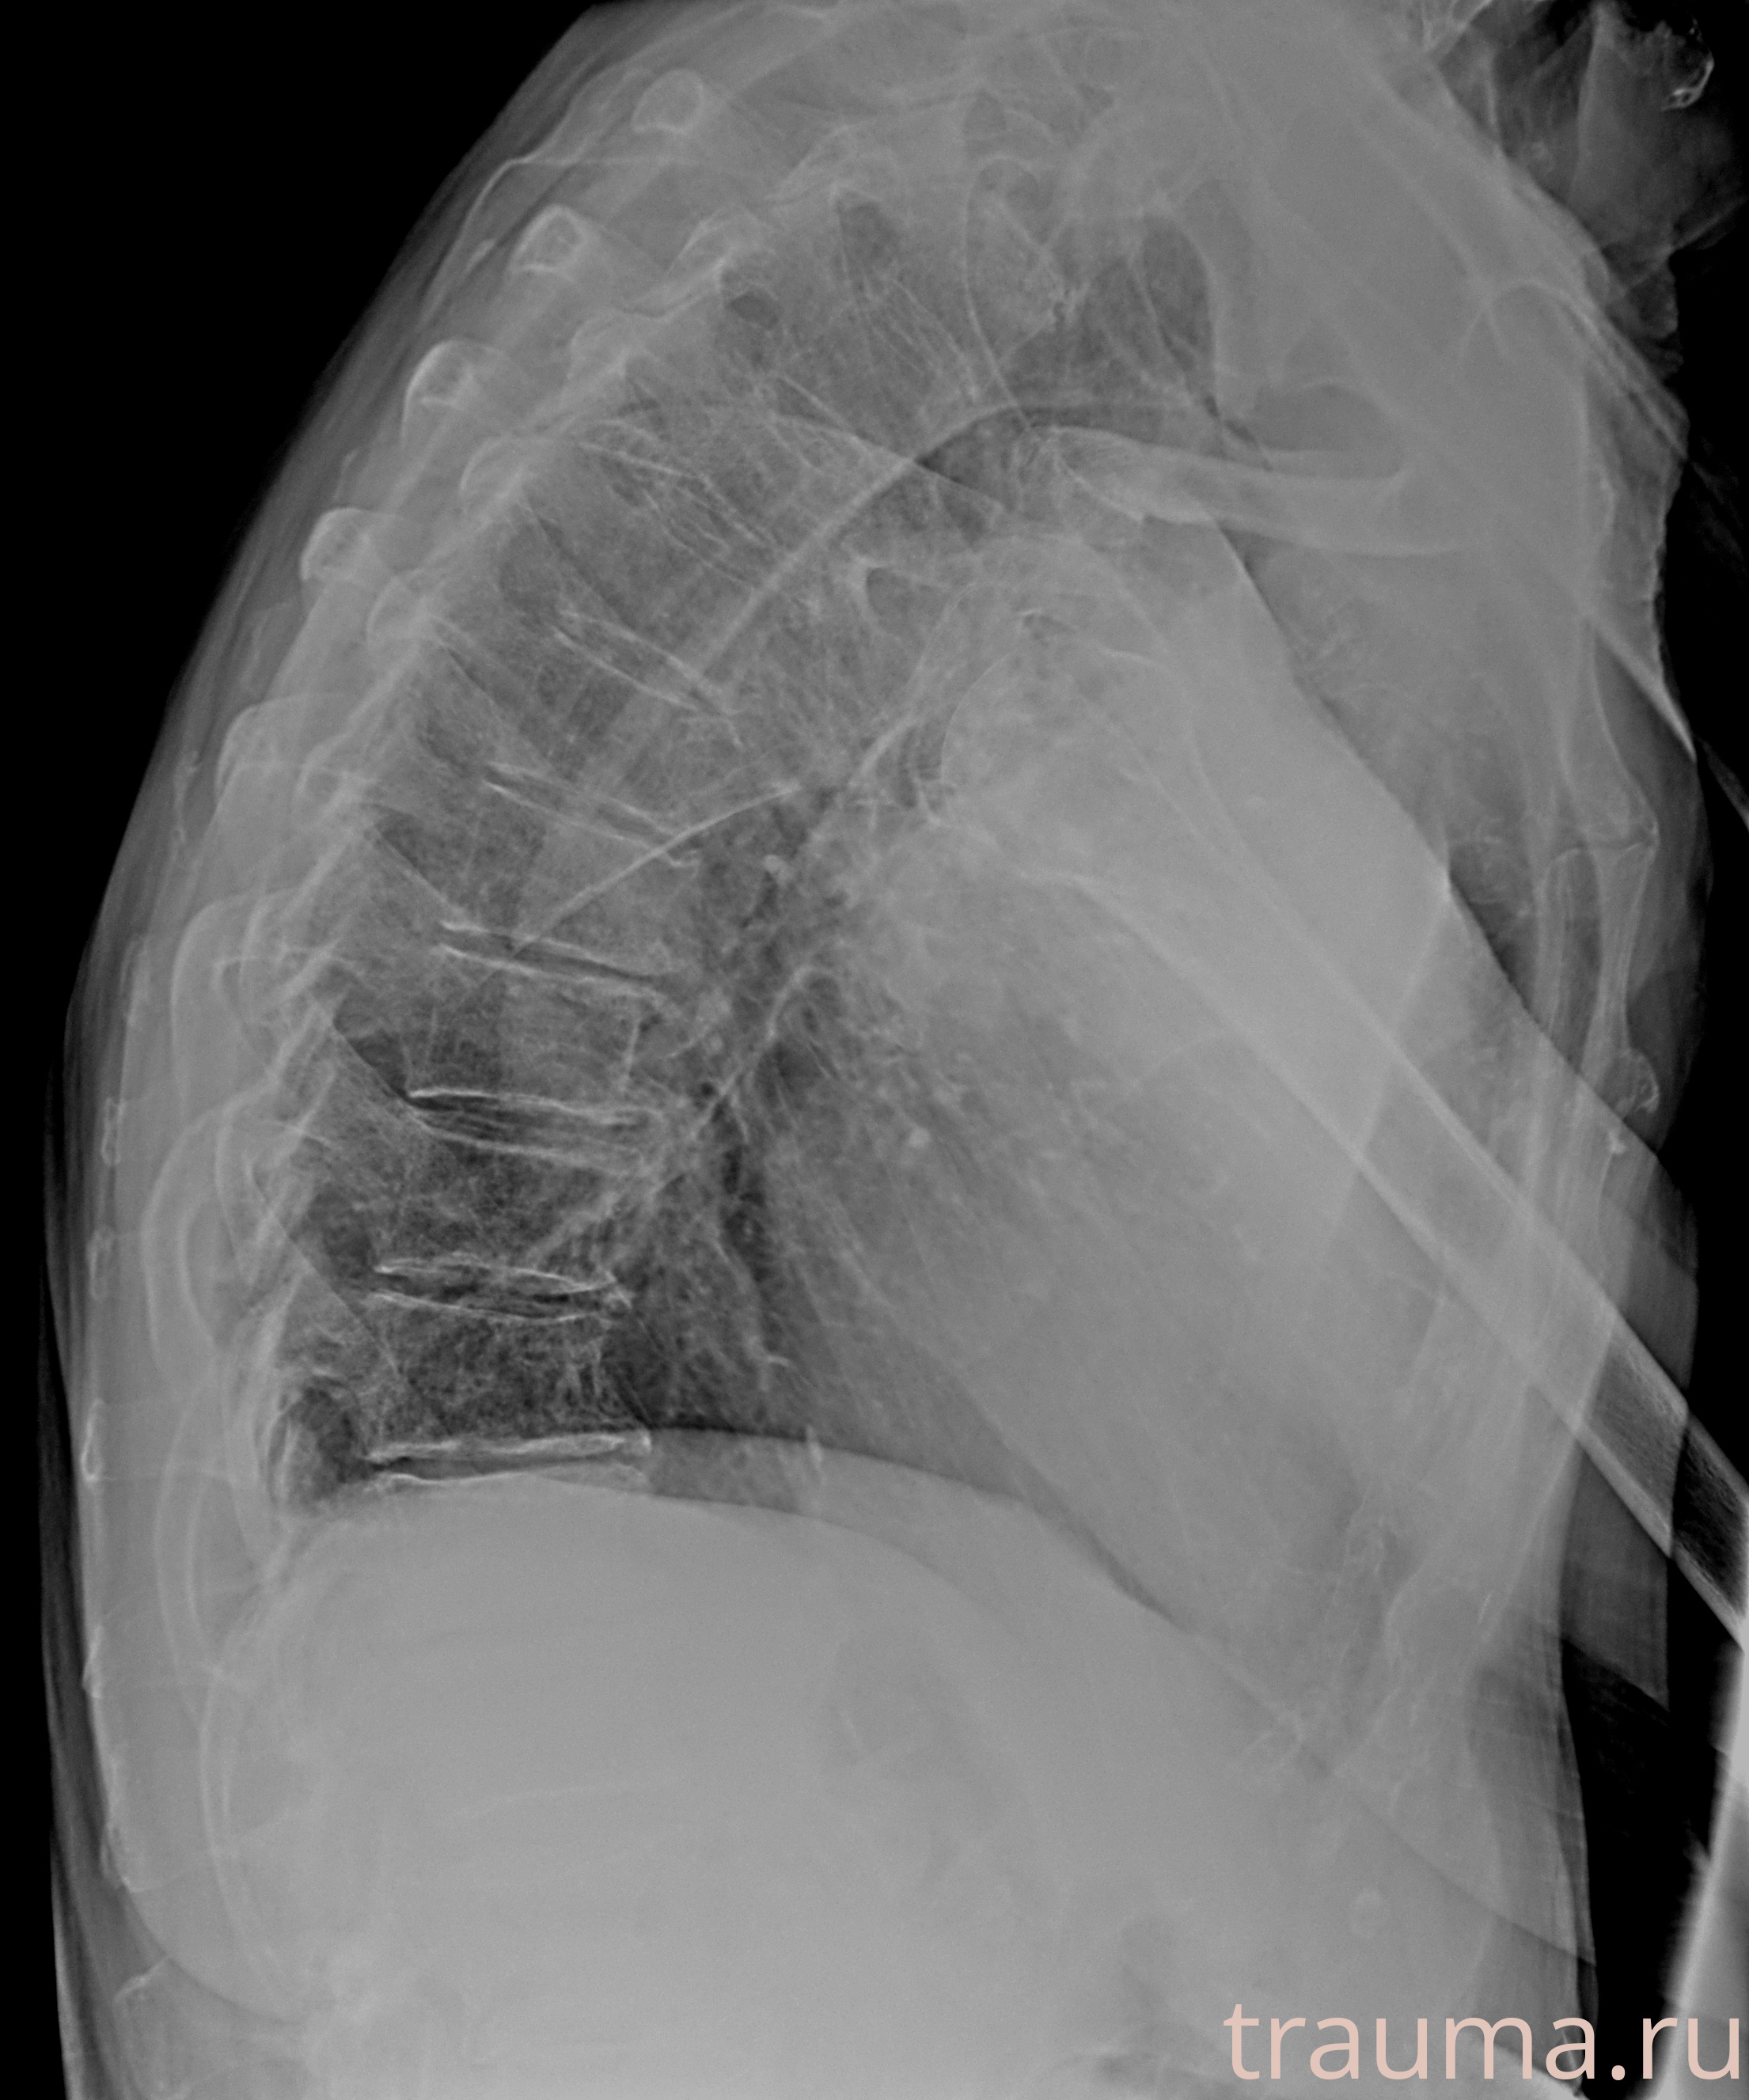

Рентген на дому: по вашему адресу приезжает врач-рентгенолог, травматолог-ортопед с мобильным рентгеновским аппаратом, проводит диагностику травмы или заболевания, делает необходимые рентгенограммы, дает рекомендации по дальнейшему лечению. Получить качественные снимки в домашних условиях возможно благодаря уникальной методике, разработанной МосРентген Центром для института  Склифосовского